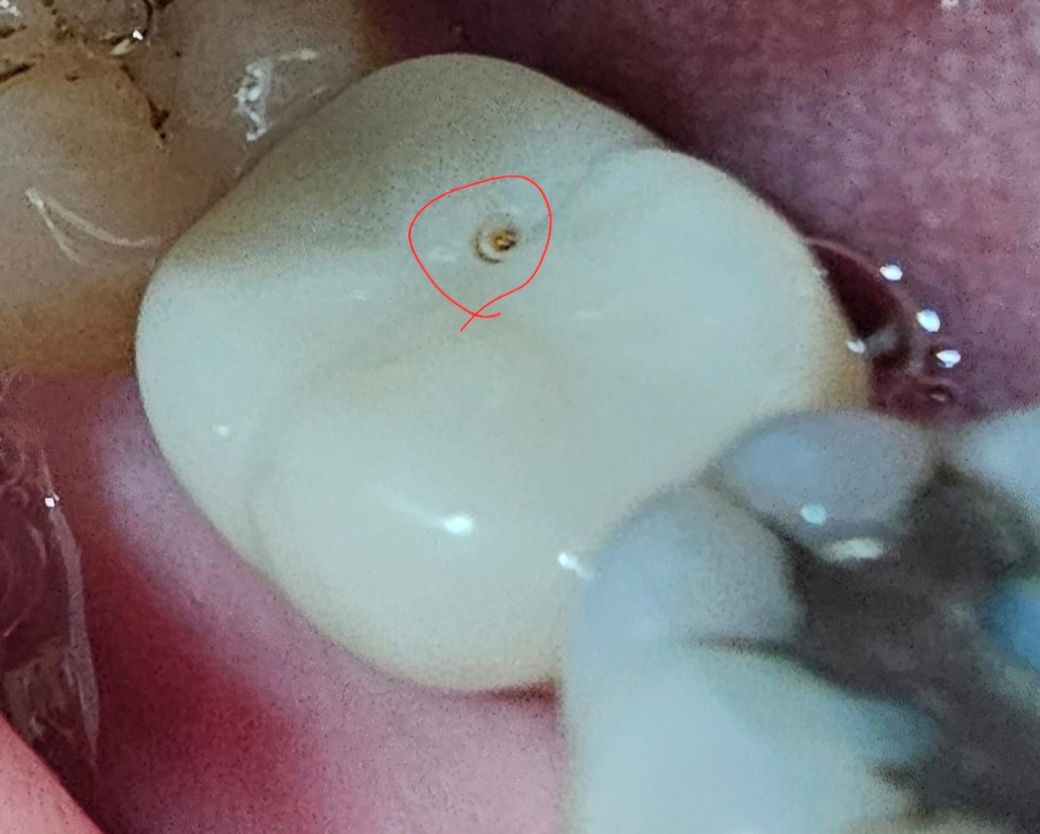

임플란트한 부위가 깨진걸까요? 레진이 떨어진건가요?

1주일 전쯤 양치를 하는데, 임플란트 한 치아에

뭔가 묻어 있더라고요. 그래서 그냥 양치를 하고 넘겼는데, 어제 양치 하는데 또 묻은게 있어, 치실 갈고리로 해당 부위를 긁어보니, 자그마한 구멍이 생겼더라고요. (첨부사진 빨간색 동그라미 부분)

이 구멍이 임플란트 위를 덮은 레진이 불상의 원인으로 소실되어,

단순히 다시 레진을 덮어 치료해주면 되는건지,

아니면 임플란트를 다시금 해야 하는건지 알고 싶습니다.

임플란트 머리를 뿌리와 연결하는 나사 구멍을 막아둔 레진이 떨어진겁니다 치과가서 다시 막아달라하세요

임플란트 나사를 조이기 위해서 만들어둔 구멍으로 보이며 깨지거나 한 것은 아닌 것 같습니다.

임플란트 보철물은 나사로 연결을 합니다. 사진에 보이는 부분은 나사를 조이는 구멍으로 보입니다.